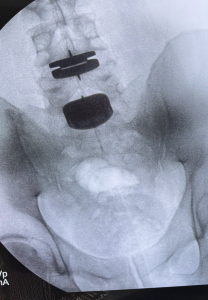

3. The Procedure Works—Really Works

Disc replacement is designed to address the three main culprits of degenerative disc pain: loss of height, reduced motion, and nerve compression causing pain. In Dr. Brusovanik's case, it did all three. He left the hospital five hours after surgery after only taking one pain pill. He had performed this very same procedure on a patient the week prior, underwent it himself the following week, and then was back to performing it the week after his own surgery. Dr. Brusovanik is now pain-free and back to practicing the very physical sport of jiu-jitsu. Experiencing the results firsthand confirmed what he had seen for years in his own patients—but with renewed conviction.